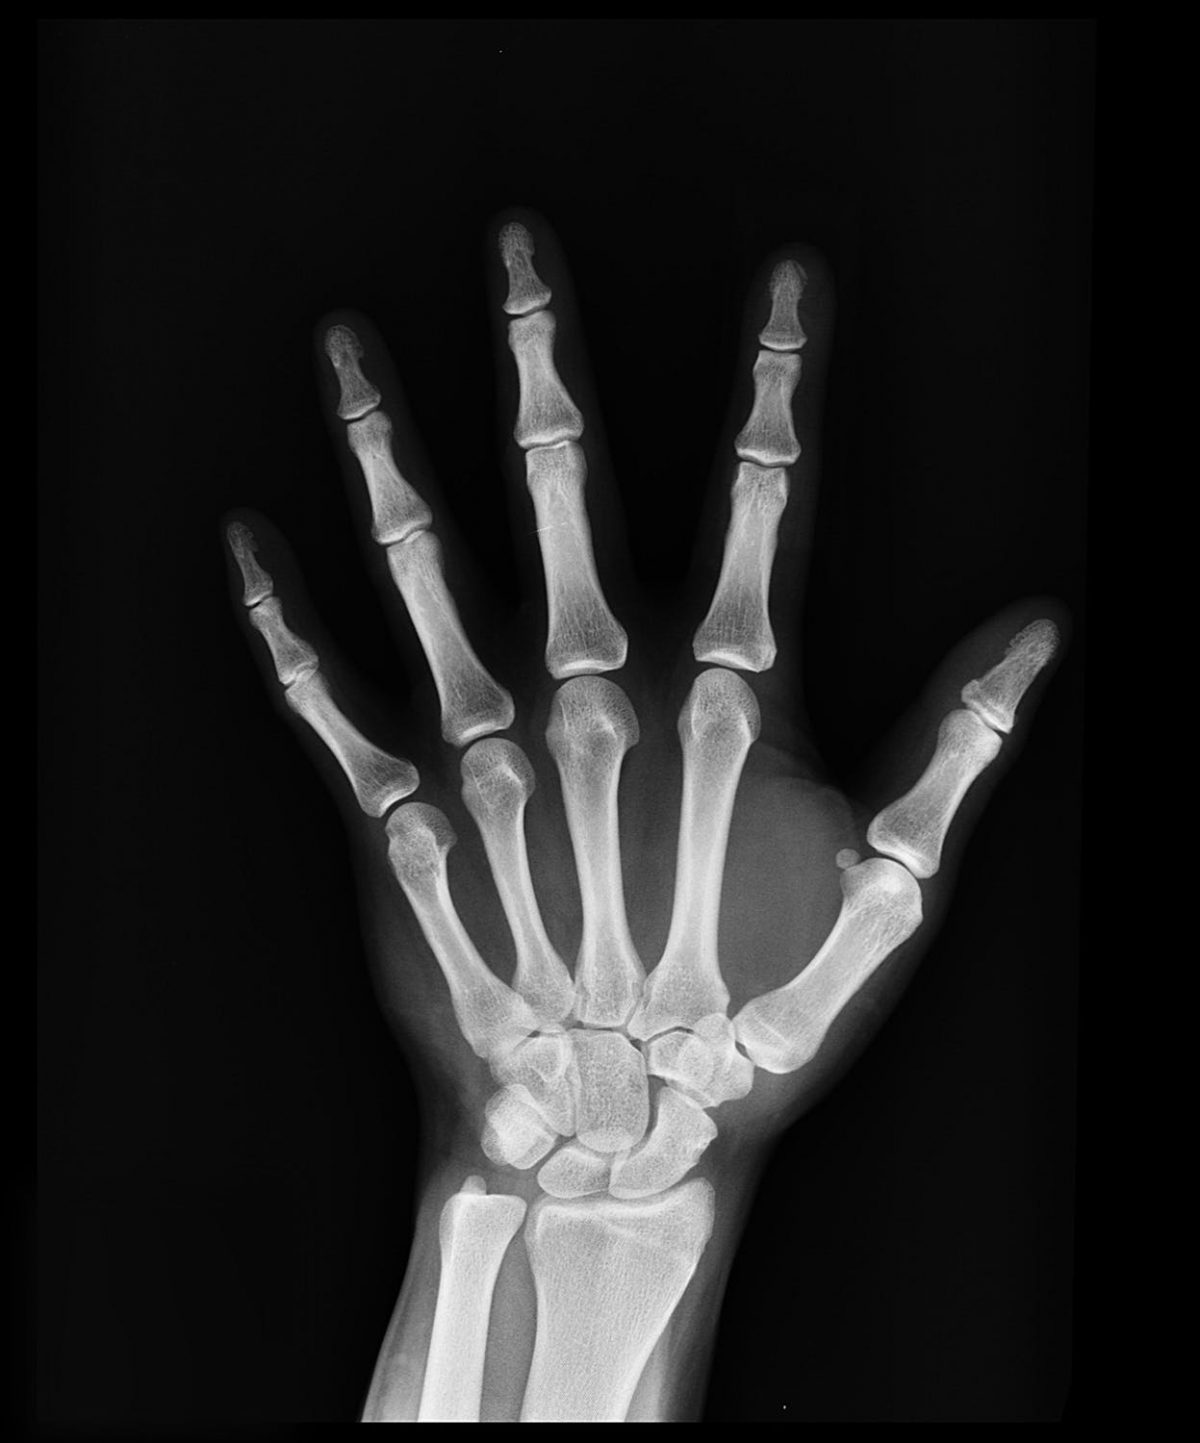

X ray hair removal when x rays were invented beauticians immediately started to use them for hair removal procedures but then discovered a few months later that their clients were coming back with atrophy ulcerations and later on cancerimage from tricho system. Moderate medical spas laser hair removal tattoo removal 1611 s catalina ave ste l70 redondo beach ca i met with marjan for a consultation she was very clear in explaining everything that she was going to do. X ray hair removal is an efficient and usually permanent hair removal method but also causes severe health problems occasional disfigurement and even death.

The very success claimed by quacks practicing hair removal with x ray proves that the skin has been destroyed else the hair would grow. It made hair fall out. By 1970 one study estimated that over one third of all radiation induced cancer in women over a 46 year period could be traced to x ray hair removal.

In the early 1920s the tricho system used x rays to remove superfluous hair. X ray hair removal finally ended after 1946 after wed seen all those terribly wounded japanese women whose radiation hair removal had been no matter of choice. It is illegal in the united states.